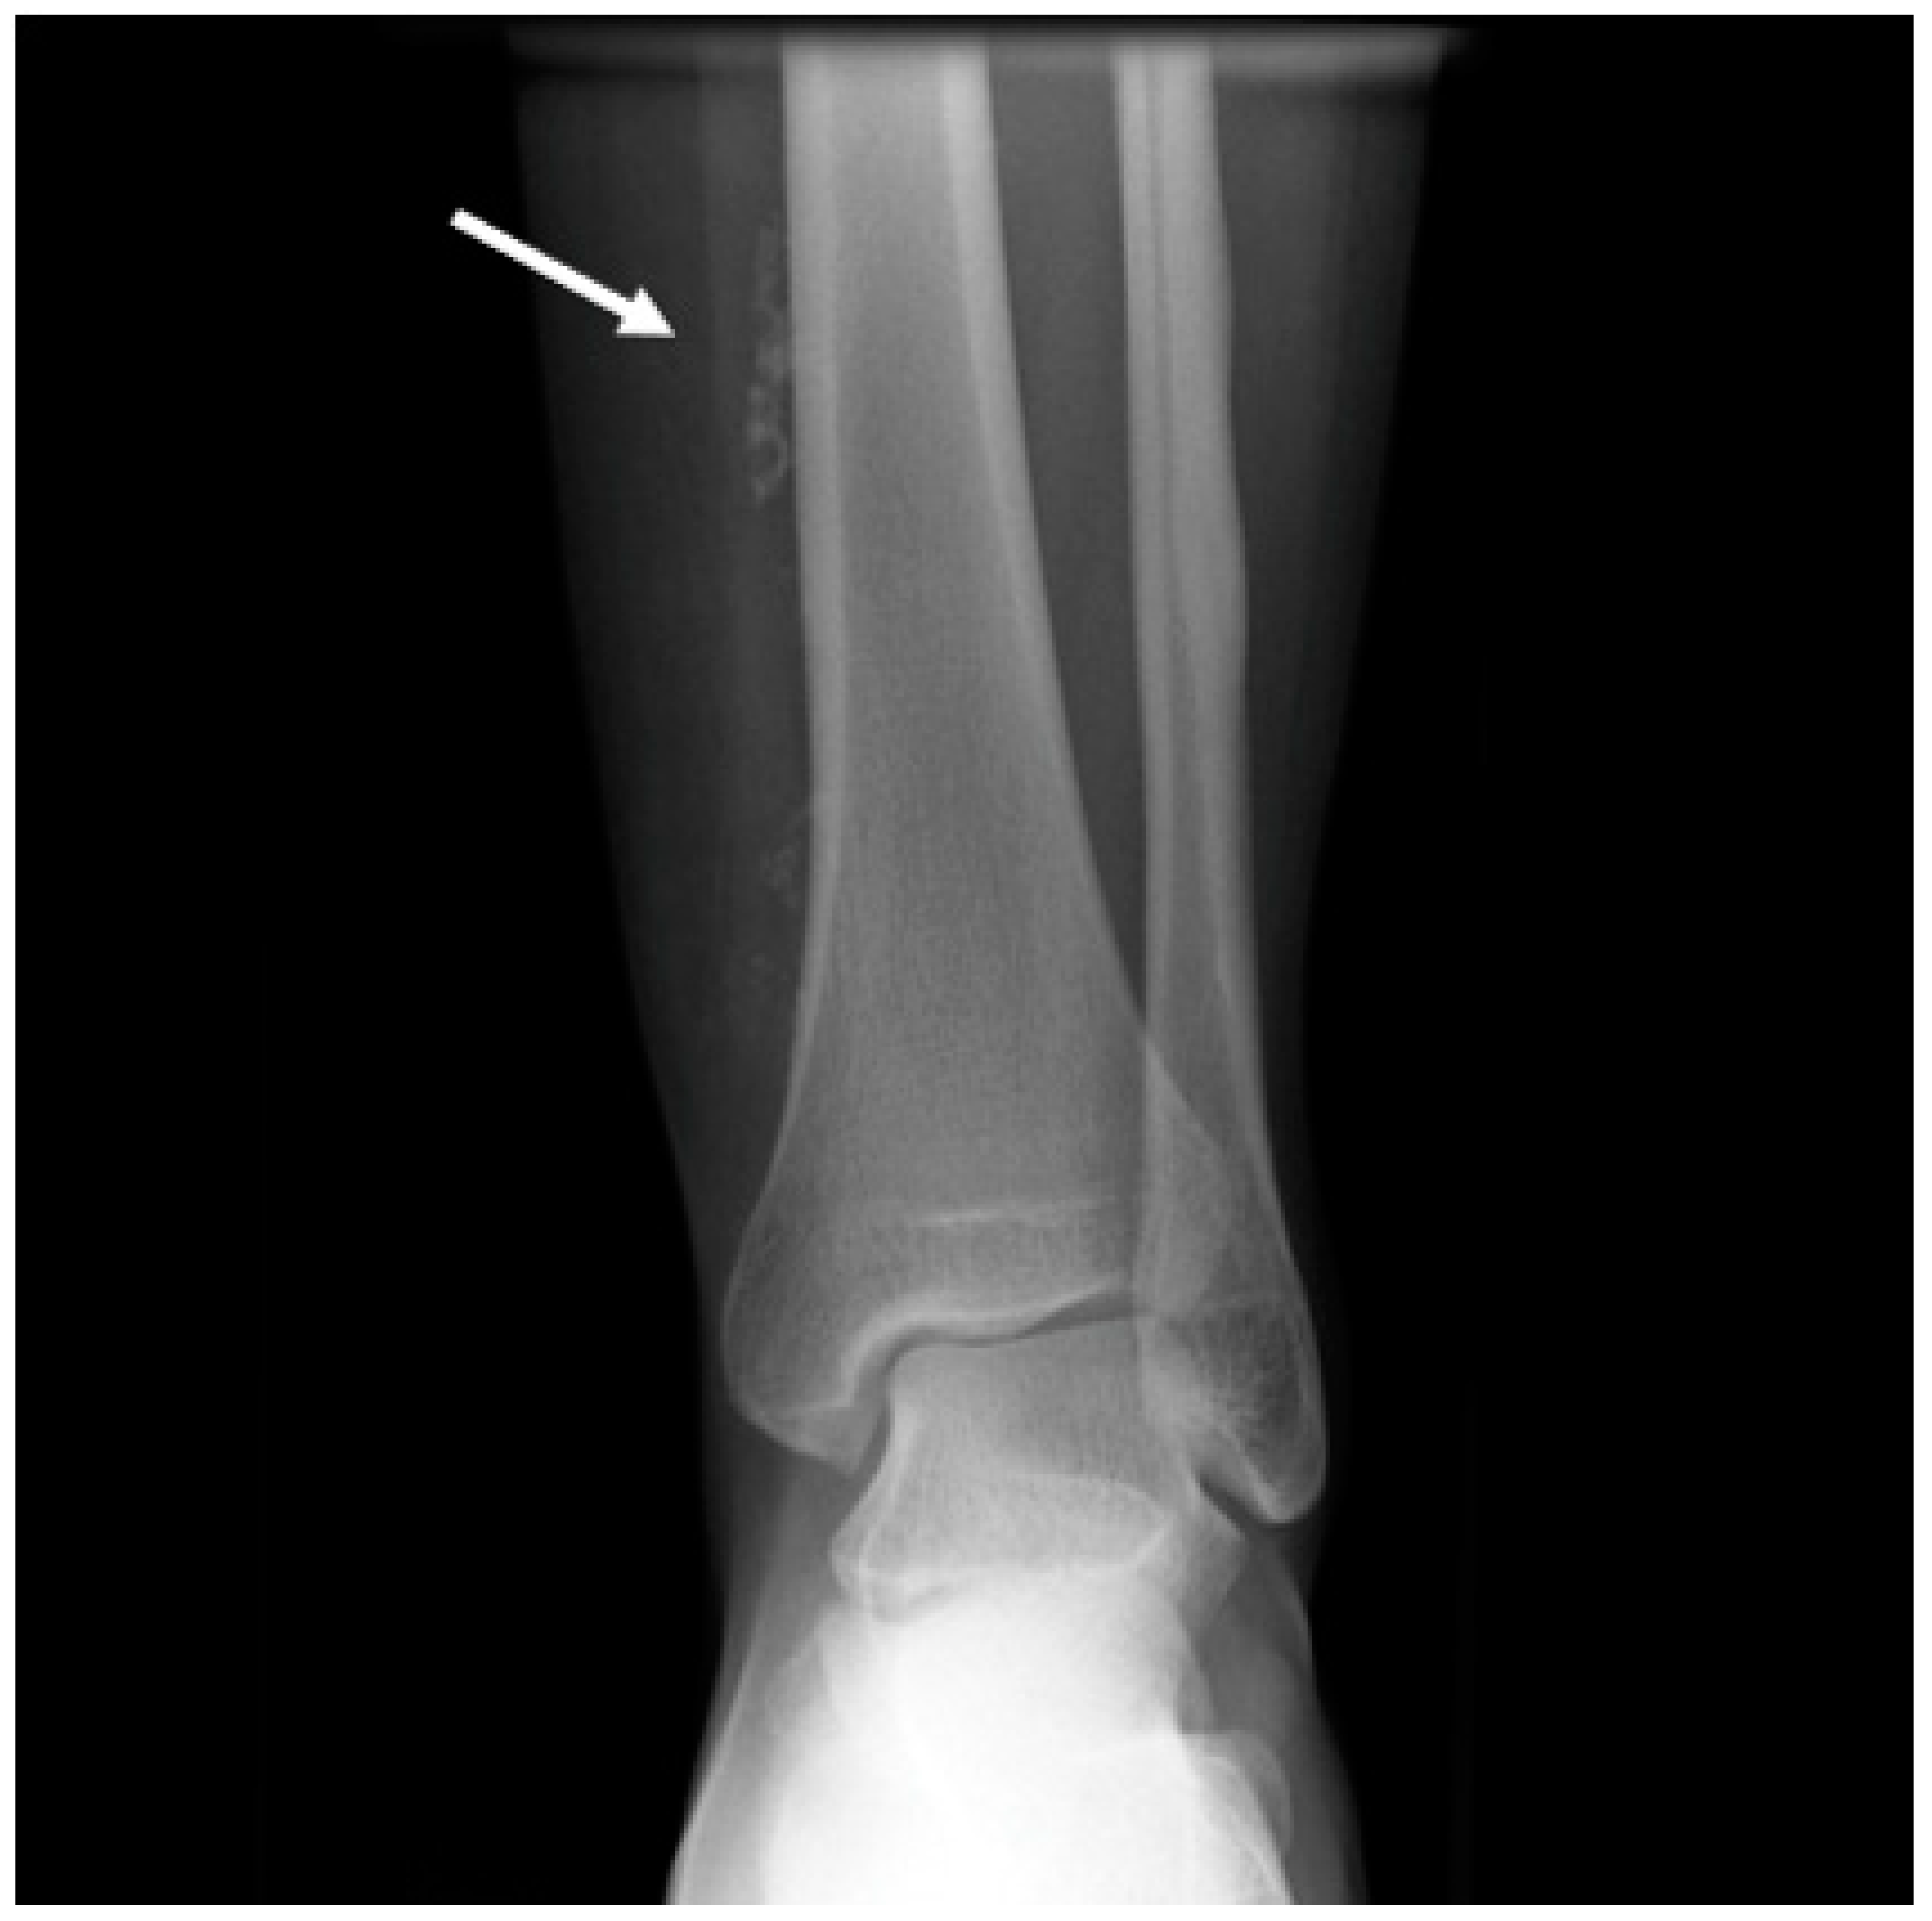

Ultrasounds can provide indications of the exact type of lesion and can help to distinguish it from other lesions. It is also possible to gather information on the morphology (size, anatomical location and depth), number and compressibility (hard, non-compressible lesions are always suspicious for a malignant nature) [44]. It can also discriminate high-flow from low-flow anomalies and frequently offers a specific diagnosis when there are characteristic features of VMs (4, 10, 15, 18, 20). The presence of arterial flow is suggestive of high-flow lesions such as hemangiomas, other vascular tumors and high-flow VMs (Figure 1).

When arterial flow is recognized on Doppler US, further considerations can be made. High vessel denseness and high Peak Systolic Velocity (PSV) can be recognized. More information can be gained by calculation of resistive index: the arteries inside high-flow VA show low-resistance flow, with low values of resistive index (RI).

Figure 1. Ultrasound imaging with power Doppler on the thigh. (A). A well-defined, solid, ovoid lesion is seen in the subcutaneous plane, without calcification or cystic changes. (B). Significant flow is noted on color Doppler with an artery entering and exiting the lesion.